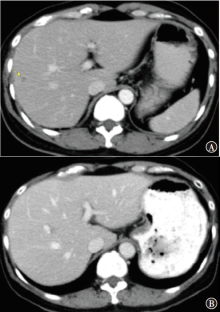

以人表皮生长因子受体2(HER2)扩增或过表达为特征的HER2阳性乳腺癌占所有类型乳腺癌的15%~20%,其侵袭性强且易复发转移,抗HER2靶向药物的应用极大地改善了HER2阳性转移性乳腺癌患者的预后。现报道1例采用伊尼妥单抗联合长春瑞滨治疗HER2阳性转移性乳腺癌患者,该患者达11年无疾病进展。